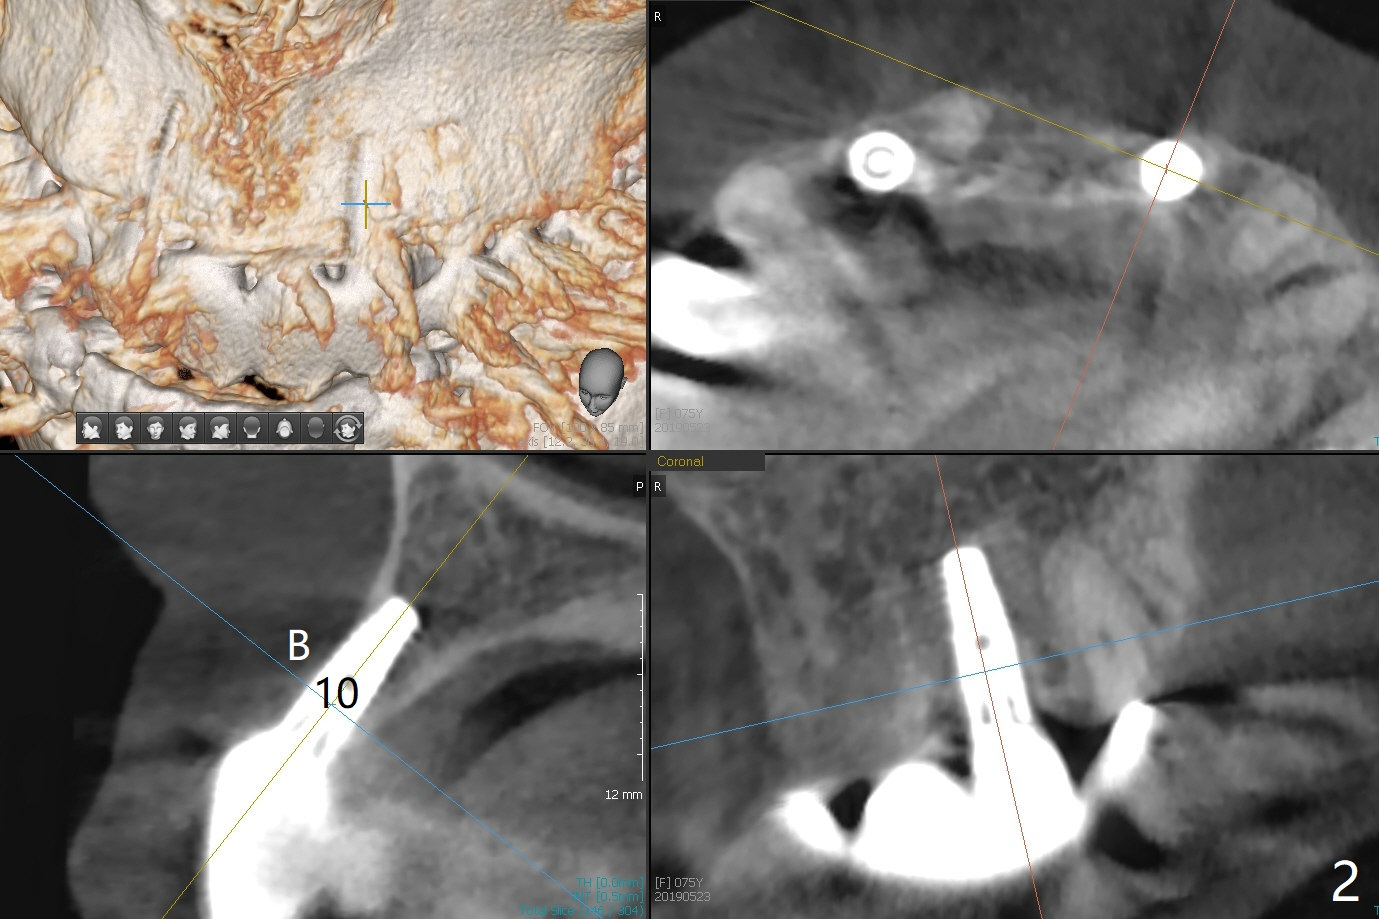

When the 75-year-old woman presents to clinic with #25 mobility, she is also concerned about gingival hemorrhage. It appears that the buccal plate is lost at #10 and 30 (Fig.2,3), as compared to #7, 19, 20 (Fig.1,4,5). Block graft may be required (Fig.6,7 for #10 for example). In fact there is tenderness buccal to the implant at #30. The patient has been using water pik and will carry it while traveling.